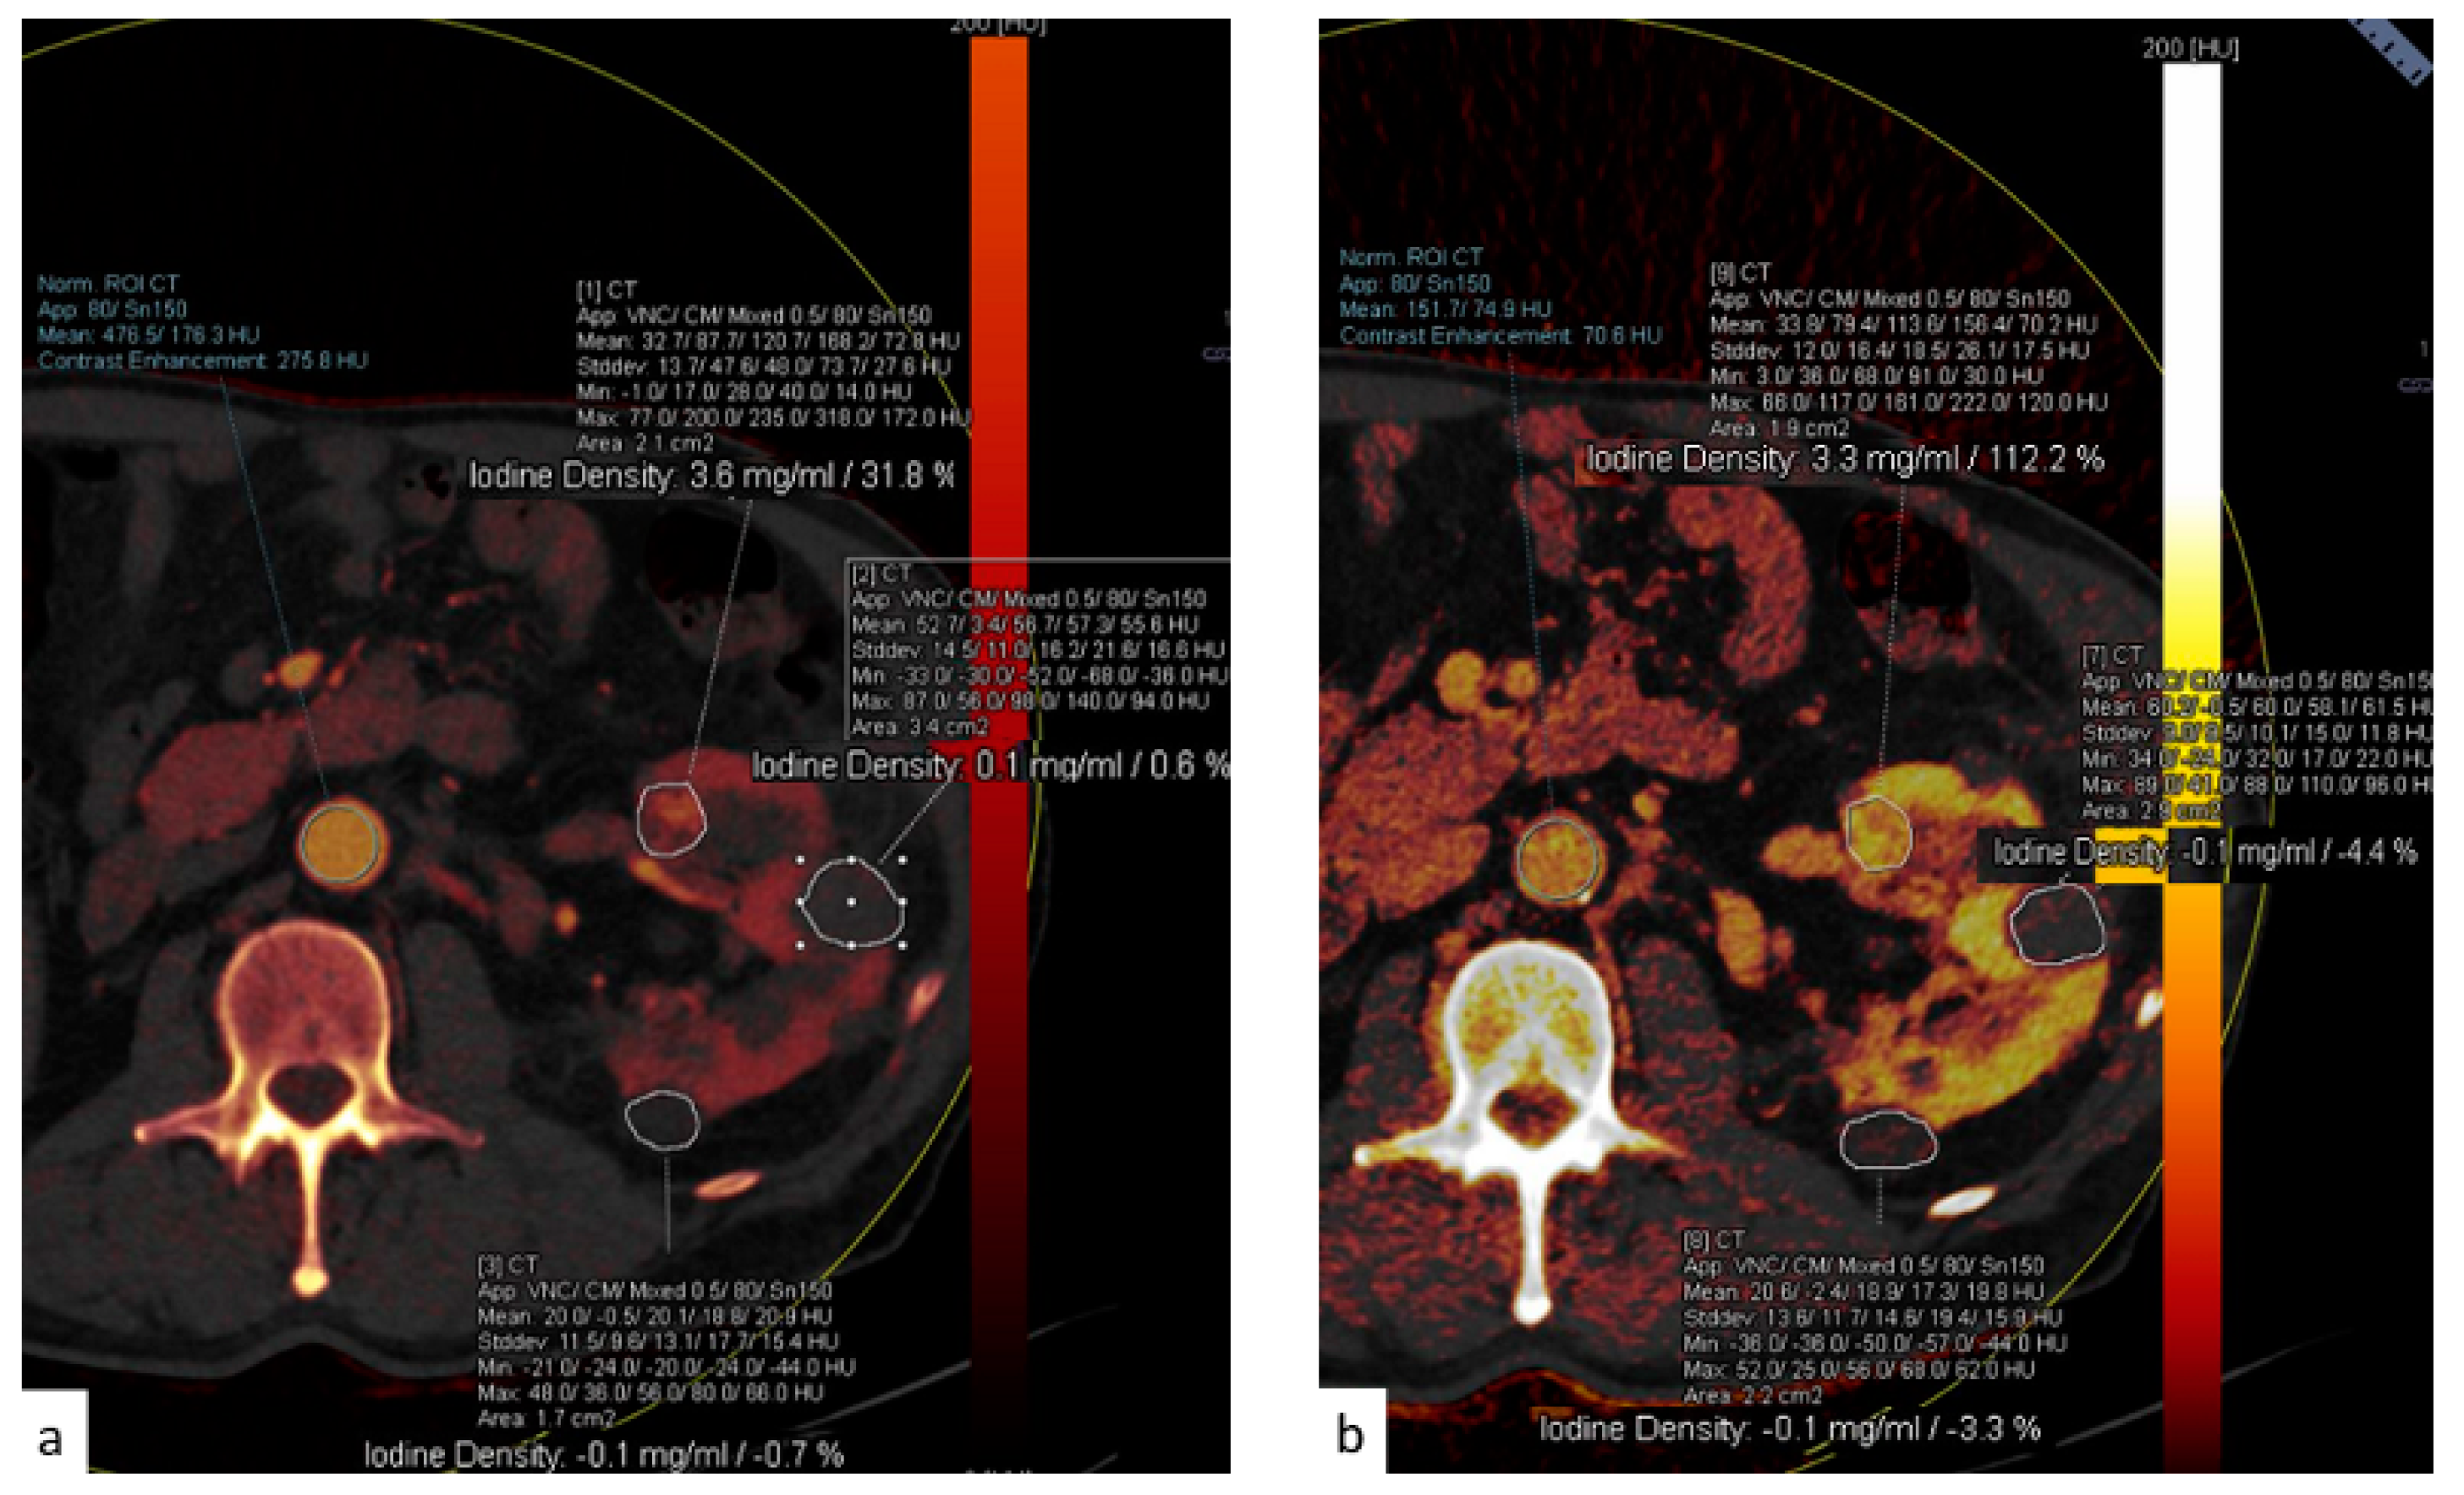

DECT images can also be post-processed to create maps that show the concentration of different components including iodine, fat, and calcium. The construction of iodine maps aids in the identification of tissues with higher or lower iodine concentrations (Figure 10, Figure 11 and Figure 12).

Figure 10.

Dual-energy acquisition of a corticomedullary phase. In (a) the iodine map shows the absence of iodine within the left renal cysts. To confirm it, a region of interest can be placed in the cyst (b) and in the aorta, to obtain the spectral curves. (c) The green curve confirms the absent contrast enhancement within the renal cyst, in comparison with the blue curve showing the enhancement within the aortic lumen.

Figure 11.

(a) Dual-energy acquisition of a corticomedullary phase with visualization of the iodine map. (b) The posterior and external renal components do not show iodine contents, whereas the anterior nodulation shows clear iodine content.

Figure 12.

(a) The spectral curve of the renal nodules highlighted in Figure 12. (b) The yellow and orange lines correspond to the two cysts.

Iodine density measurements have different applications. First, they enable the management of incidentally detected renal masses, allowing their characterization from a single examination and avoiding additional imaging and diagnostic timing delays [73]. Virtual monochromatic images demonstrated better correction of beam hardening artifacts, reducing the degree of pseudo-enhancement in intraparenchymal renal cysts, and allowing for a more confident diagnosis, when compared to standard CT acquisitions [74].

Iodine density measurements and iodine overlay images provide a visual depiction of enhancement that helps in the discrimination between avidly enhancing clear cell renal cell carcinoma and hypoenhancing papillary renal cell carcinoma [75] and is also particularly useful in the assessment of treatment response when using targeted antiangiogenic agents for clear cell renal cell carcinoma [76] and in patients treated with ablation [77].